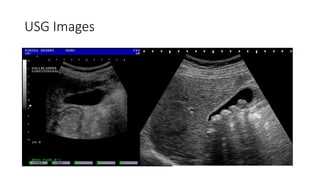

Radiological Investigation: USG

• Findings will be

1. Presence of Dilated IHBR is s/o of Obstructive Jaundice.

2. CBD Diameter (Normal is 7-8 mm) if it is more than 8 mm

suggestive of dilatation.

3. Gall Stone and CBD Stone Can be identified.

4. Mass in CBD can be detected if it is >2 cm.

5. Pancreatic Head Malignancy detected if >2 cm.

6. Presence of Liver Metastasis and Ascites.

USG Images